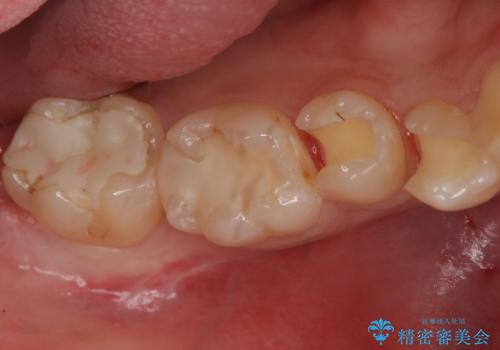

今回は虫歯の治療のみのご希望であったため、掲載している写真の右側2本(口腔内の手前側)を治療していきました。

写真の左側2本(口腔内の奥側)は適合が悪いことが見て取れると思います。

こういった場所は汚れがたまりやすく虫歯のリスクが高くなっているため、適合の良い修復物にやりかえることをお勧めします。